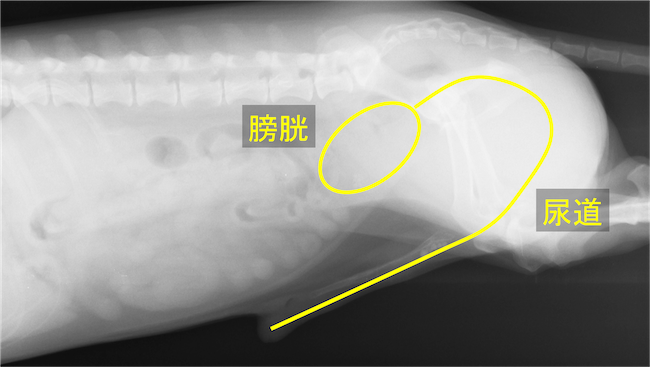

膀胱と尿道の位置

尿道内に結石が5つ連なって認められる